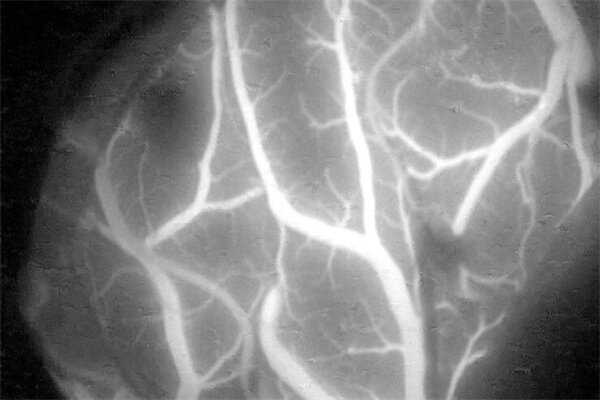

在术中荧光辅助视频血管造影术中,外科医生可以通过观察血流来确定血管是否通畅。

GLOW800 增强现实荧光 (AR 荧光) 和 ICG 吲哚箐绿造影剂搭配使用,可以呈现出一张白光和荧光效果同时存在的实时血流视图,在颅脑解剖结构和血流之间形成清晰可见的轮廓。

这项先进的功能可在一张视图中同时呈现色彩自然的颅脑解剖结构和实时血流,不必中断手术过程在自然的显微镜图像和平面黑白近红外视频之间来回切换。

查看色彩自然的组织,全面感受深度知觉,并获取实时增强的血流视图,在脑血管手术中更加自信地作出准确的治疗决策。

• FL800 术中影像血管造影模块:配合 ICG 吲哚箐绿造影剂使用时,该功能可帮助神经外科医生清晰地看见实时血流情况。